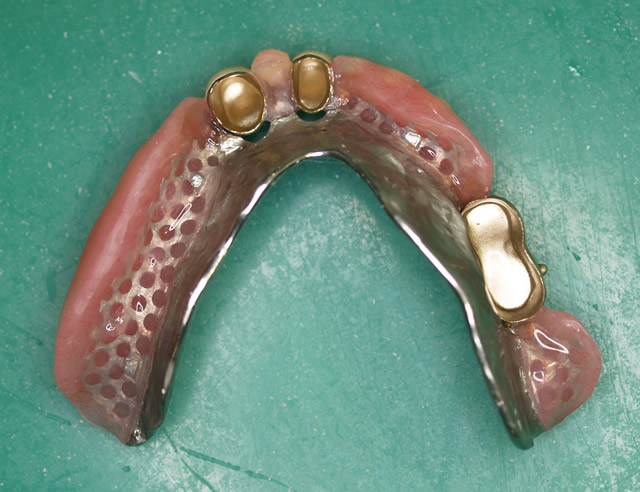

症例 4

鳥取県 53才 男性

入れ歯の相談例を記載します。

私は現在53才の男性ですが、下顎(したあご)には歯が3本しかなく困っています。

※注釈 この方の上歯は全部自分の歯でした。こういった上顎が自分の歯の場合は、下顎に負担が掛かり、通常の作り方では上手くいかないことが多いのです、コーヌスで治療しました。

【治療後のメール】

こんにちは!ご無沙汰しております。今年の春の約3ケ月、お世話になりました鳥取のXXです。

ブラッシングが行い易く、また患者さんもお手入れを良くされていたことから良好を保持できたのだと思われます。

違和感なく、と感想を述べておられていますが、これは私の独自の型の採り方なので、コーヌスをどこで作っても全てそうだということでありませんので念のために。